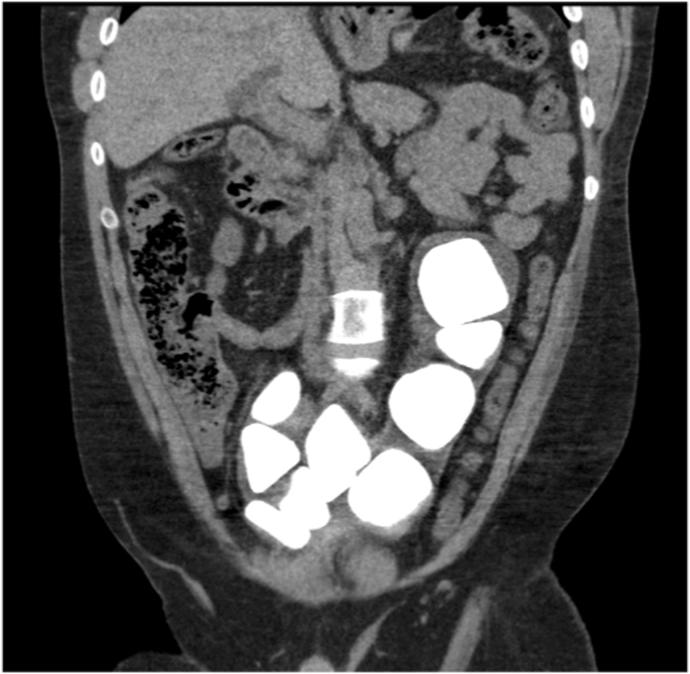

Large bladder stones in an augmented bladder - An open approach to a big problem.

Bladder augmentation can be a valuable life-changing operation for patients with bladder dysfunction, however, are associated with several complications that require long-term management. One of the most common complications seen in these patients are bladder calculi. If bladder stones are left untreated, they can become extremely large and cause pain, urinary tract infections, or difficulty emptying the bladder. We present the case of a patient with an augmented bladder who had numerous large bladder stones and his management.